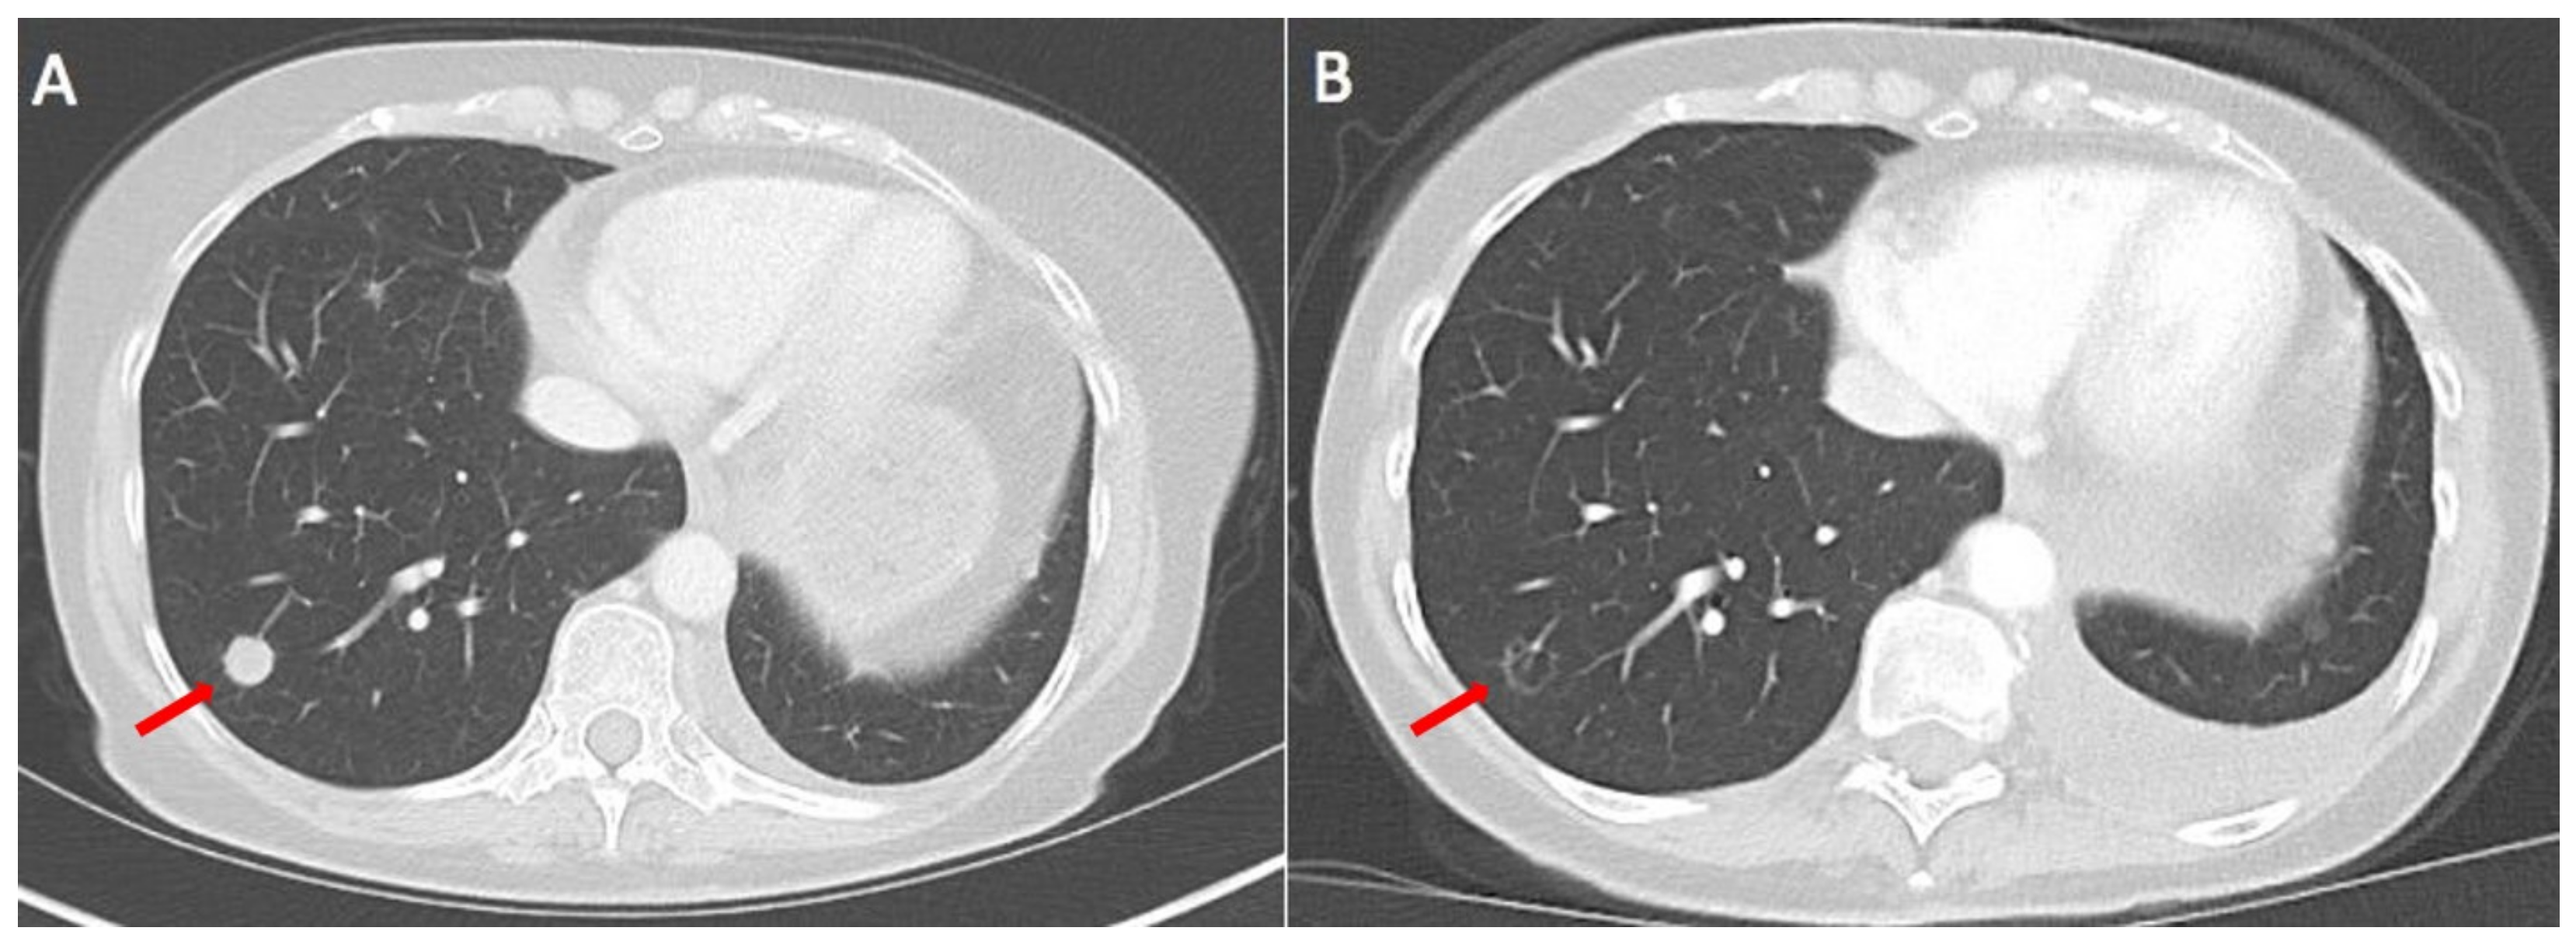

2. Case Report